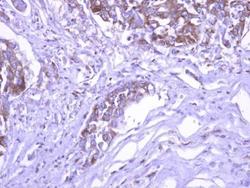

Supportive validation

- GeneTex (provider)

- Experimental details

- SEC3 antibody detects EXOC1 protein at cytoplasm on Colon cancer xenograft by immunohistochemical analysis. Sample: Paraffin-embedded Colon cancer xenograft. SEC3 antibody (GTX119659) dilution: 1:500.